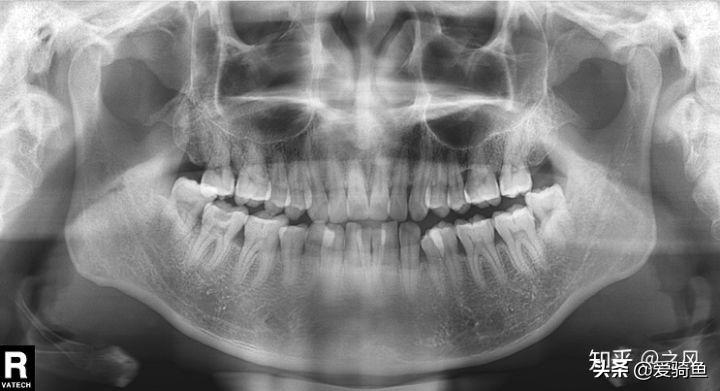

排隊(duì)等待叫號(hào),進(jìn)去后張嘴檢查下,讓去拍片子,應(yīng)該就是我之前去的其他牙診所機(jī)構(gòu)的口掃,這里沒(méi)有給我電子照片,下面是以前拍的。

口掃

智齒